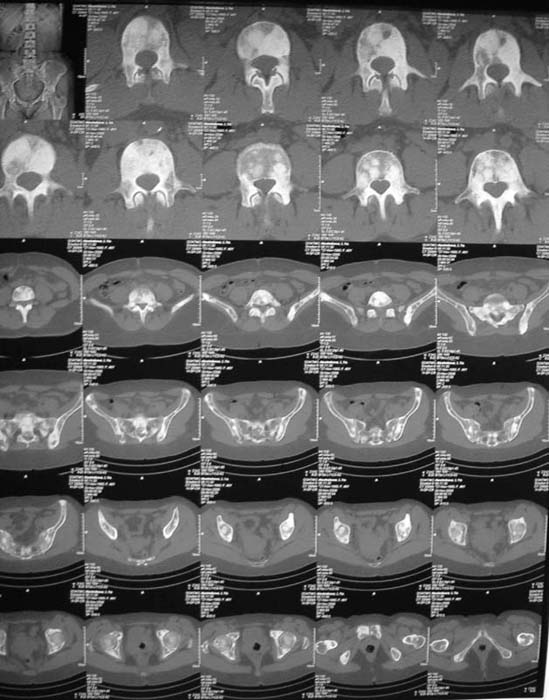

При МРТ (29.10.06) обнаружены диффузно-очаговые изменения в пояснично-крестцовом отделе позвоночника предположительно вторичного характера.

В октябре 2006 г. по поводу маточного кровотечения (менопауза 4 мес.) выполнено УЗИ - гиперплазия эндометрия, полипоз. Операция - удаление полипа, выскабливание полости матки. Цитологический анализ - пласты переходного климактерического эндометрия.Проведено комплексное исследование. В приложении: рентгенограммы и томограммы поясничного отдела позвоночника; радиологические исследованиямолочной железы, ЖКТ, почек, грудной клетки, анализы.УЗИ (18.12.06.) щитовидной железы, молочных желез - без патологии (умеренный фиброз по ходу млечных протоков).

Остеосцинтиграфия 4.12.06. - активный остеобластический процесс в поясничном, нижнегрудном отделах позвоночника, костях таза.Местными онкологами онко-процесс исключен. Фтизиатрический и онкогематологический диагнозы исключены.

Диагноз, исходя из сцинтиграфии, предположительно метастазирование без определения первичного очага. Я сделал бы КТ органов и костей таза. Следующим шагом желательно взять биопсию, возможно из крыла таза (будет проще) после четкой визуализации очагов на КТ...